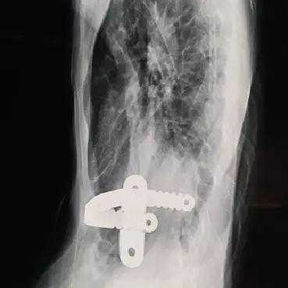

The patient is a 16-year-old male who has been diagnosed with pectus excavatum in childhood but experienced no discomfort in daily life. At the age of 15, he underwent Nuss procedure during which a bar was placed in his chest wall. However, the depression in his chest wall persisted after the surgery, and he even developed new severe deformities. As the deformities gradually worsened, the patient developed scoliosis, and his entire chest wall became completely distorted, eventually losing its basic shape. Later, the patient underwent another minimally invasive surgery for spontaneous pneumothorax, during which the surgeon ligated bilateral pulmonary bullae without treating the chest wall deformities. Ultimately, because of the severe deformities and breathing discomfort, the patient came to our hospital for treatment.

The patient was diagnosed with severe complex chest wall deformities accompanied by scoliosis. The heart was severely compressed and shifted to the left thoracic cavity.